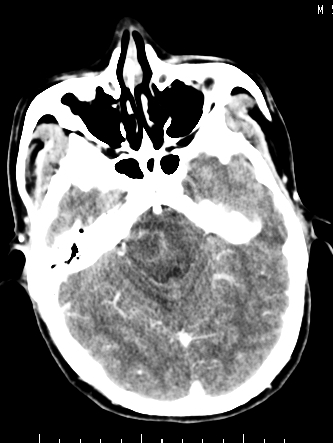

m/50,头昏头痛1月,近3天感觉左半肢体活动不利,自述半年前呈患肺tb,腰穿脑脊液未见特殊改变。现做头颅ct请大家会诊。

结核性脑膜炎,结核瘤,梗塞灶三症并存,提示颅内结核感染可能性大。

感染性病变;脑干脓肿(脓肿壁形成期),基底节及内囊(脑炎期)。顺便问一句,该病人是不是抵抗力很差,有没有糖尿病。

右侧基底节区缺血性脑梗塞.脑干区考虑结核.